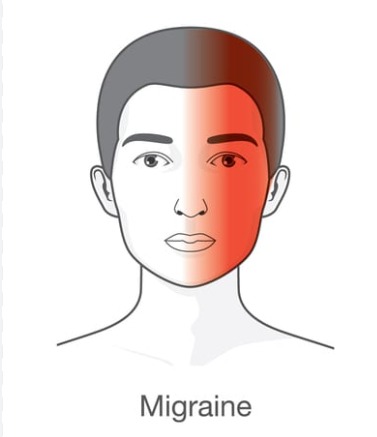

Migraine/ Headache

सर दर्द